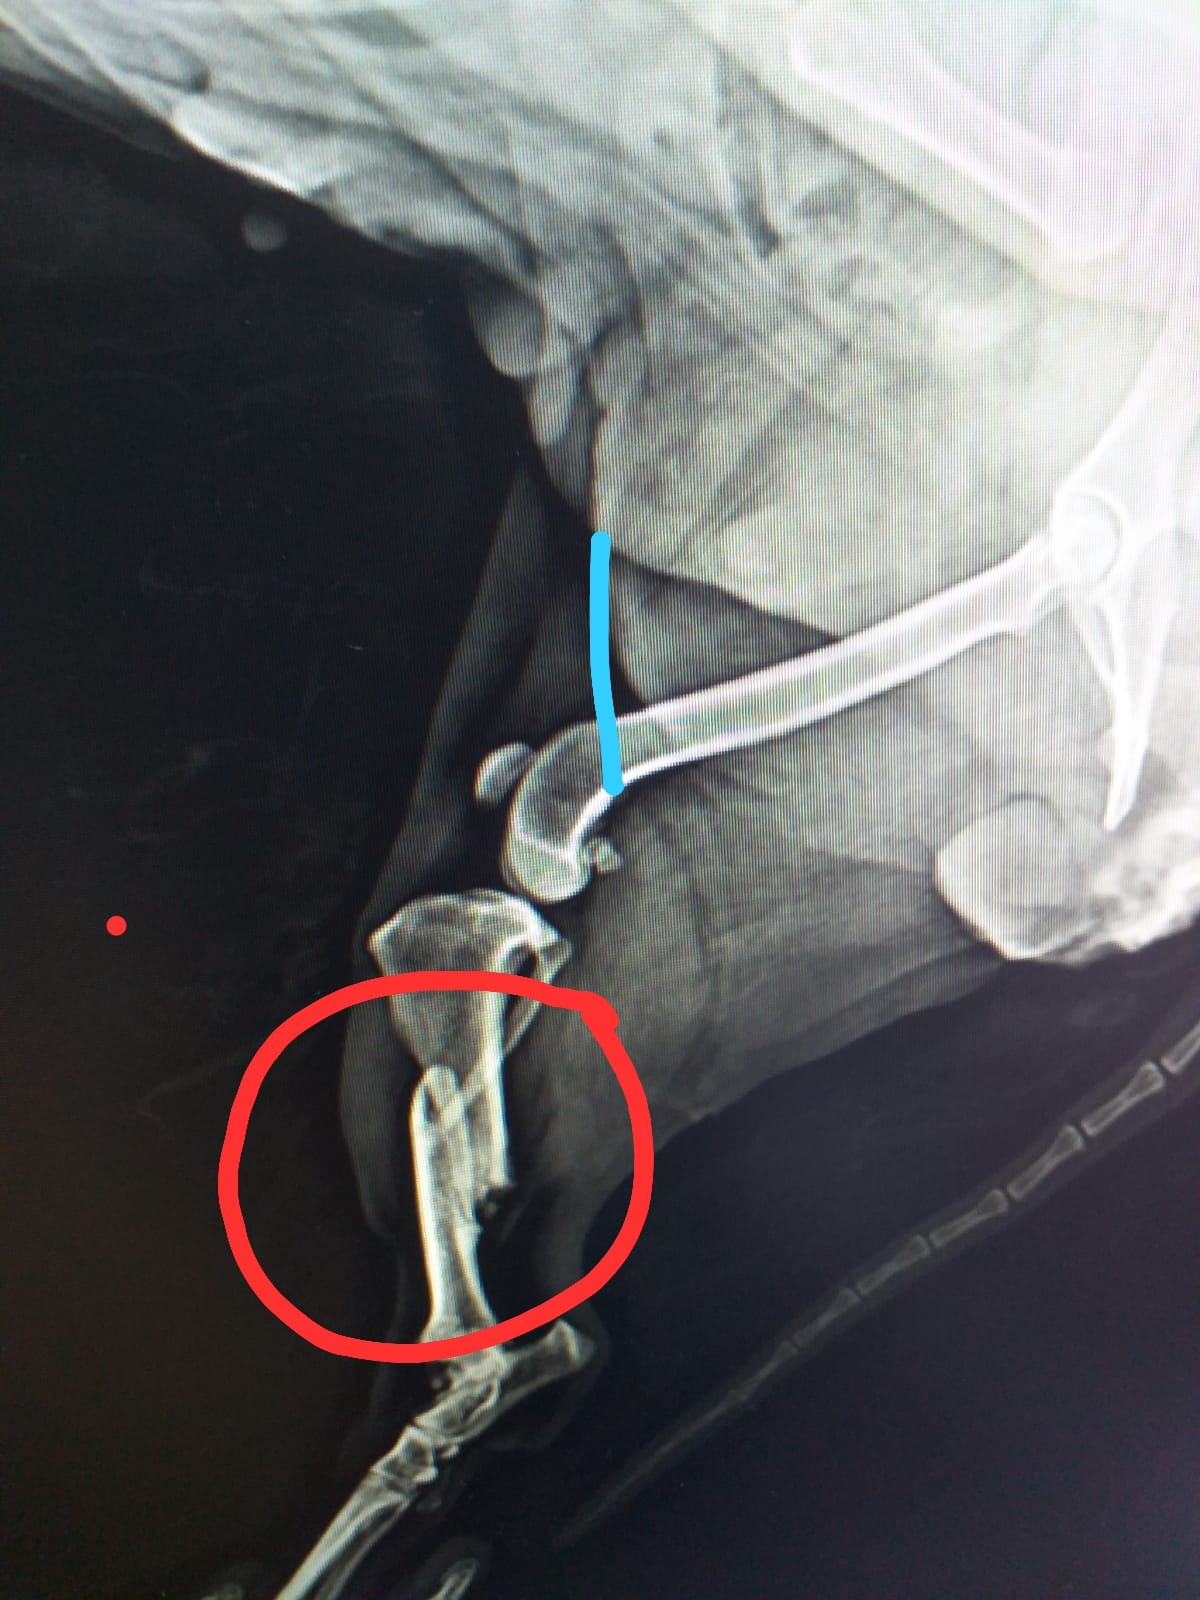

Zitat von Redaktion neu am 3. Oktober 2021, 15:26 UhrDas kleine Ömchen Mini haben unsere Kollegen eher zufällig in einer spanischen Perrera entdeckt. Dort drohte sie inmitten der großen Hunde unterzugehen und so haben sie die kleine Maus kurzerhand mitgenommen. Doch Mini konnte mehr schlecht als recht laufen und hatte offensichtlich starke Schmerzen. Mit Hilfe von Röntgenbildern wurde ein komplizierter Bruch an einem Hinterbeinchen und an dem anderen eine Patellaluxation festgestellt. Leider war der schon einige Wochen alte Bruch nie versorgt worden und musste deshalb operiert werden. Die OP ist gut verlaufen, aber da Minis Knochen nicht mehr die jüngsten sind, verheilt der Bruch leider nur langsam. Zur Unterstützung bekommt Mini mittlerweile zweimal wöchentlich Physiotherapie, was ihr sehr gut tut.

Das kleine Ömchen Mini haben unsere Kollegen eher zufällig in einer spanischen Perrera entdeckt. Dort drohte sie inmitten der großen Hunde unterzugehen und so haben sie die kleine Maus kurzerhand mitgenommen. Doch Mini konnte mehr schlecht als recht laufen und hatte offensichtlich starke Schmerzen. Mit Hilfe von Röntgenbildern wurde ein komplizierter Bruch an einem Hinterbeinchen und an dem anderen eine Patellaluxation festgestellt. Leider war der schon einige Wochen alte Bruch nie versorgt worden und musste deshalb operiert werden. Die OP ist gut verlaufen, aber da Minis Knochen nicht mehr die jüngsten sind, verheilt der Bruch leider nur langsam. Zur Unterstützung bekommt Mini mittlerweile zweimal wöchentlich Physiotherapie, was ihr sehr gut tut.